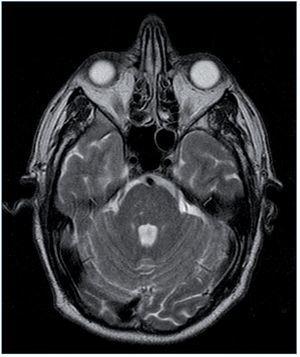

Entre las pruebas complementarias destacaba un ecocardiograma en el que se objetivó una dilatación y una hipertrofia biventricular grave, con una disfunción sistólica grave de ambos ventrículos, una disfunción diastólica tipo III y una insuficiencia mitral funcional moderada (fig. 1). Ante estos hallazgos se realizó coronariografía, que descartó lesiones coronarias. En el mismo procedimiento se visualizaron las arterias renales, que no mostraron datos de estenosis. Durante el ingreso, el paciente presentó un episodio de amaurosis fugax, por lo que se realizaron una TC y una RM cerebrales, que mostraron enfermedad isquémica de pequeño vaso (fig. 2).

Figura 2. Resonancia magnética del caso clínico 2. Infartos lacunares hemorrágicos antiguos de predominio en tronco cerebral.